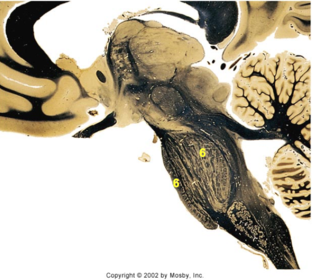

| Head of caudate | |

| Anterior commissure | |

| Thalamus | |

| Substantia nigra | |

| Optic tract | |

| Dentate nucleus | |

| Pons | |

| Longitudinal pontine fibers | |

| Uncus | |

| Superior cerebellar peduncle | |

| Red nucleus | |

| Corticospinal tract (dark) | |

| Pontine nuclei (pale) | |

| Transverse pontine fibers (dark) | |

| Inferior olive | |

| CTT | |

| Medial lemniscus | |

| Nucleus cuneatus | |

| Superior colliculus | |

| Inferior colliculus | |

| Optic nerve | |

| Cerebellum | |

| 4th ventricle | |